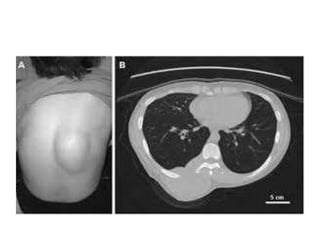

Common site encapsulated lipoma

 Neck

 Back

 Shoulder

 Upper limb

CLINICAL FEATURES

Most lipomas are small (under one centimeter

diameter) but can enlarge to sizes greater than six

centimeters.

Localized

Lobular

Fluctuant

Mobile

 Exhibit “Slip sign”.

(They move easily when pressure is placed on them)

Skin free

Soft

Onexamination they do not exhibit differential

warmth.

Lipomas areusually painless soft and non tender.